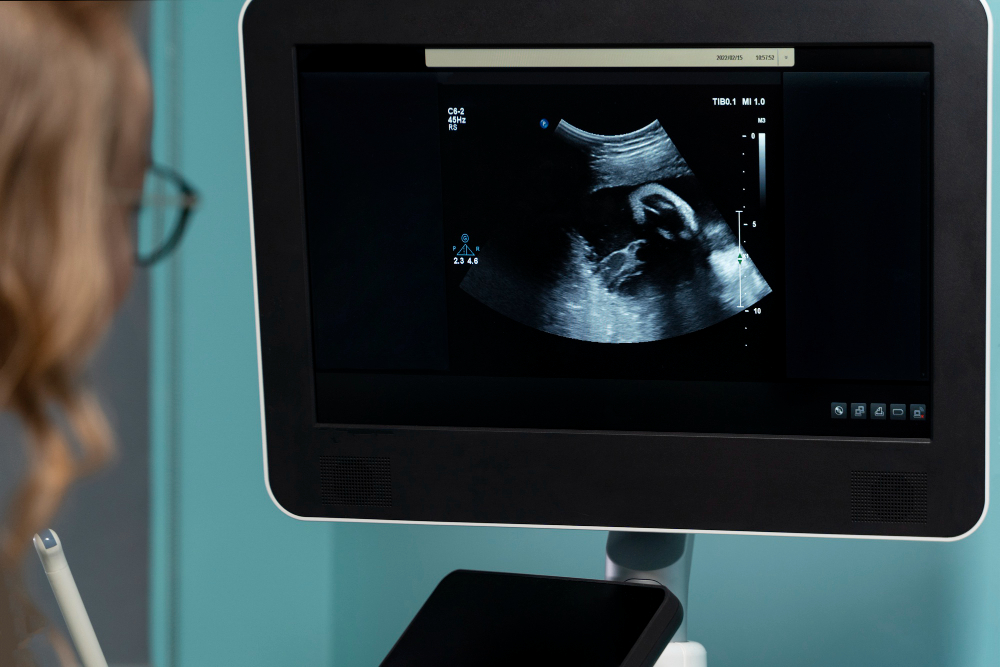

How Is the Scan Performed?

The placental localization scan procedure is simple and painless. Most often, it is done with a standard ultrasound machine. Here is how the process usually works:

• You lie down on an exam table.

• The technician applies a cool gel to your belly.

• A small device called a transducer moves over your skin.

• The device sends sound waves to create images of your uterus and placenta.

• The doctor reviews the images to find the placenta’s position.

• Sometimes, if the placenta is hard to see, a vaginal ultrasound may be needed. However, this is safe and only takes a few extra minutes.